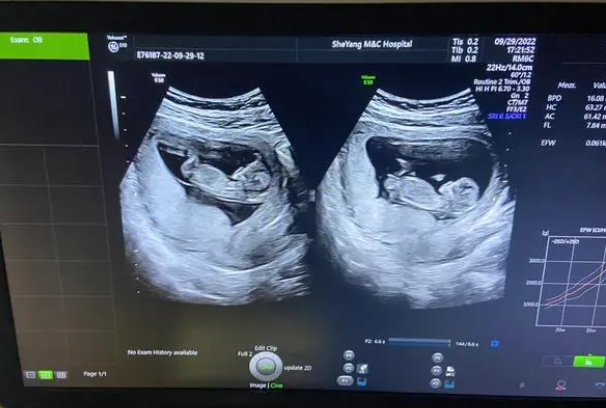

三甲医院四维彩超费用2000多和500的区别在哪里?

怀孕快20周了,本来说这几天去三甲医院预约一个四维彩超检查,但是现在却遇到了选择难题,我发现现在的四维彩超有费用2000多的和500的,我本来以为越贵的应该看的越清楚,但是我发现有人说两者使用的仪器相差不多,所以我就更奇怪了,既然仪器一样,那么费用上为何差距这么大,问问了解的朋友们,知道2000的和500的区别在哪里吗?